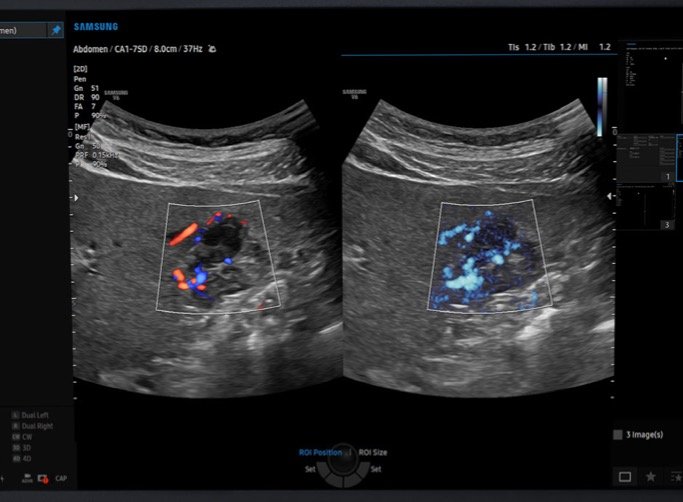

ECOGRAFIE ED ECOCOLORDOPPLER

Presso il Poliambulatorio San Giuseppe di Pontedera diversi specialisti effettuano esami diagnostici. Tra gli strumenti utilizzati, segnaliamo un ecografo di nuova generazione che integra l’Intelligenza Artificiale.

Presso il Poliambulatorio San Giuseppe di Pontedera esegue esami ecografici utilizzando un ecografo di ultima generazione dotato di Intelligenza Artificiale.